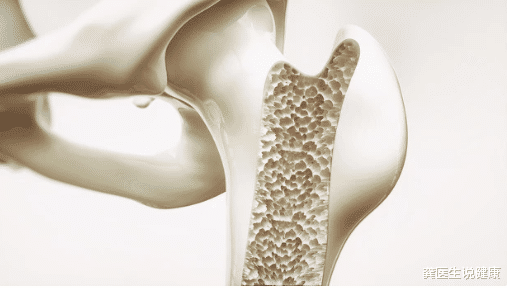

张女士是妥妥的上班族 , 半年前陪爸爸跑了趟医院做体检 , 居然被查出来严重的骨质疏松 , CT上显示张爸爸的骨密度已经-2.8 。 回家路上张爸爸还在一直重复说“补了一辈子钙 , 为啥还是得了骨质疏松呢?”

张女士听了内疚了好久 , 觉得作为子女 , 这方面的知识了解得太少了 。 以前张爸爸说腰酸背疼 , 就只是一味地买钙片 , 认为就只是上了年纪缺钙了 。 去医院这么一检查 , 才知道医生说钙不能盲目补充 , 能把钙质留在骨骼里才是有用的!

2、盲目补钙的危害

补钙不能跟风 , 盲目的补钙只会是让你吃进去的钙都是游离的钙离子 , 大部分不吸收都排泄出去了 , 少部分在体内 , 错误沉积到软骨 , 内脏 , 血管等 。 还会因此造成骨质增生、结石、血管钙化等危害 。 因此需要抓住钙离子 , 把它牢牢固定在骨骼中 , 才能避免错误不改带来的危害 。

【龚医生说健康|补了一辈子钙,为什么还会骨质疏松?骨科教授:补钙不可跟风,牢牢锁住才算事】小贴士:患有骨质疏松的骨骼是非常脆弱的 , 甚至有些轻微的动作也可以引发骨折 , 如咳嗽、打喷嚏、用力提重物等等 , 平常走路也要避免湿滑的地方 , 以免摔倒 。